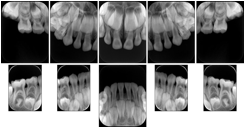

3. A dental provider wishes to capture a series of DICOM IO images for the patient’s dentition. The tooth morphology, teeth are divided into molars, premolars, canines and incisors, and a number of images for each jaw. The anatomic information was captured utilizing the triplet of schema. This standard code sequence is based on ISO 3950-2010, Dentistry - Designation system for teeth and areas of the oral cavity.

Every IO image should have anatomic information either through the primary or modifier sequence.

In most standard cases, images are oriented in structured layouts. These structured displays are useful to be shared between providers for reference purposes.

Table OO.1.1-1 shows structured display standard templates, where Viewset ID is based on the Japanese Society for Oral and Maxillofacial Radiology (JSOMR) classification provided by JIRA (Japan Medical Imaging and Radiological Systems Industries Association, www.jira-net.or.jp). Expected or typical teeth to be imaged location, region and designation codes are based on ISO 3950-2010, Dentistry - Designation system for teeth and areas of the oral cavity. For all the hanging protocols listed in OO.1.1-1, the value to use for Hanging Protocol Creator (0072,0008) is "JSOMR" and the value to use for Hanging Protocol Name (0072,0002) does not include "JSOMR" (e.g., "DL-S001A", not "JSOMR DL-S001A").